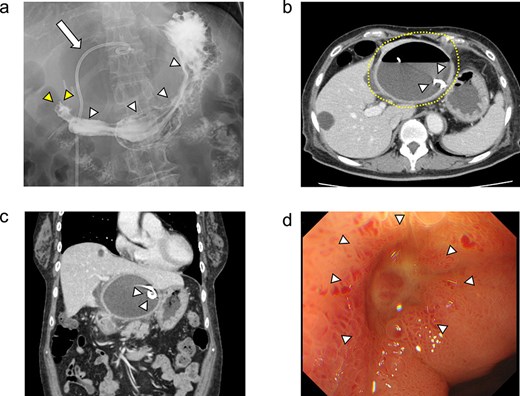

Because the hepatic cyst showed chronic inflammation and did not disappear, on day 42, the surgery was performed laparoscopically for the infected hepatic cyst (Fig. 3a). The cyst wall was opened, and a large amount of purulent fluid was discharged (Fig. 3b). Hepatic-cyst deroofing was performed (Fig. 3c–e). A depression was found in the lumen of the fenestrated cyst near the duodenal bulb, which was thought to be the penetration site between the hepatic cyst and the duodenum (Fig. 3f), and the depression was closed (Fig. 3g). One closed drain was placed at the site of the fenestrated hepatic cyst (Fig. 3h). The histopathological examination revealed no evidence of malignancy of the cyst wall.

(a–h) Operative findings during the patient’s laparoscopic surgery. (a) Inflammatory tissue adhesions were observed on the peritoneum, omentum, and hepatic cyst. (b) A large amount of purulent fluid was discharged from the opened hepatic cyst. (c, d) The hepatic cyst wall was resected at the junction of the hepatic cyst and the liver parenchyma using the LigaSure™ vessel sealing system (Medtronic, Dublin, Ireland). (e) The laparoscopic hepatic cyst deroofing was completed. (f) A depression in the lumen of the fenestrated cyst near the duodenal bulb was observed, which was thought to be the penetration site between the hepatic cyst and the duodenum. Arrowheads: The depression in the lumen of the fenestrated cyst near the duodenal bulb. (g) The depression was closed using a 3–0 Vicryl® suture (Ethicon, Cornelia, GA, USA). (h) After the peritoneal lavage, one closed drain was placed at the site of the fenestrated hepatic cyst.